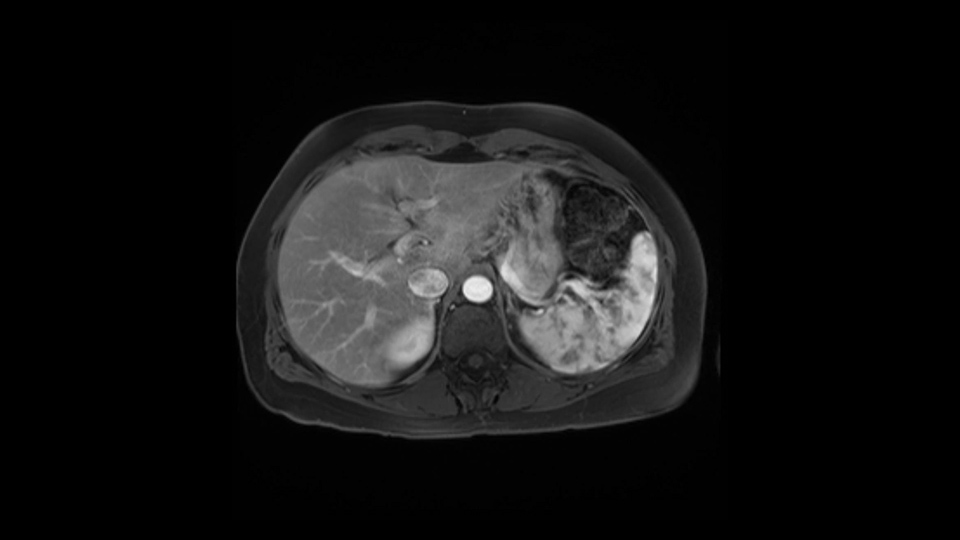

In reviewing this patient’s CT scan, first of all, the lesion is again cystic with a very thin wall. I anticipate that it will be delicate and potentially friable. And therefore the risk of rupture exists and we need to be very careful in how we handle the pancreas and the tumor throughout the procedure.

Hi my name is Carol-anne Moulton, I’m one of the surgeons here at TGH and an associate professor in the department of surgery. So I’ve had the ability to look at the MRI of this case that I’ve been asked to comment on. It has a mucinous or what appears to be a mucinous cystadenoma in the tail of the pancreas. To me, it looks like a pretty straightforward case. I agree with the decision to remove the tumor or cyst, give that it is unilocular and large and likely a mucinous cystadenoma. My preferred method of doing this particularly in a benign situation would be a laparoscopic distal pancreatectomy with or without the spleen.

The preoperative MR is very very important; any scan for that matter. Whether it is a pancreatic protocol CT scan or the MR as presented, the diagnostic imaging plays a very big role. And with this we see that it’s a very well-defined cystic focus in the body of the pancreas. Although there are septal enhancements, very well demarcated, but there is no vascular involvement. However, the mass appears to be in contact with the splenic vessel, and the mass is also a little bit in touch with the left adrenal and also the loop of bowel. So looking at this, basing on the features, I think it’s probably a mucinous cystic lesion, it could possibly be a pseudocyst. But basing on the history, it appears like there is no history that would point out to a pseudocyst. And not an IPMN as well; I don’t see any side branches from the MRCP and the MR scan and although there is no axial T2 images available, and I truly find it easier to identify the septations on T2, and the hepatic cyst that is visible on this scan makes it hard to differentiate it from a simple or complex cyst which may be considered in a mucinous neoplasm with cystic or mucinous metastasis. Basically the contrast would help us in identifying the enhancing mural nodules or septations in the cysts. The MRCP is definitely helpful to identify if there is any side branch, if we are considering any IPMN.

So first, I'll show you the scan. Here's the traditional view, where you see the cyst, which is in the body of the pancreas. And you see over here, it's got a quite thick wall. And going a little bit back also, here you see a septation which is very important, because I think a septation is what separates this from, for instance, the pseudocyst of the pancreatitis. And also the location of the cyst you see here, abutting the adrenal gland and going down a bit more, it's also quite close to a bowel loop. So when thinking about this cyst: female, the location in the body of the pancreas, thick wall, septation, and as you can read in history, it was basically asymptomatic, so no signs of pancreatitis. So, this probably all points towards a mucinous cystic neoplasm.